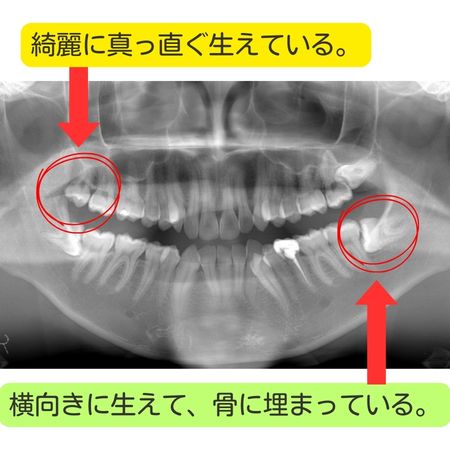

現代人は顎が小さくなっている傾向があり、その結果、

- 横向き・斜めに生える

- 一部だけ歯ぐきから出ている

- 骨の中に完全に埋まっている

といった状態になりやすくなります。

問題のないまっすぐ生えている親知らず

親知らずが以下のような状態であれば、必ずしも抜歯の対象にはなりません。

- まっすぐ正常な向きで生えている

- 上下でしっかり噛み合っている

- 歯みがきがしやすく、清掃状態が良い

- 周囲の歯や歯ぐきに炎症がない